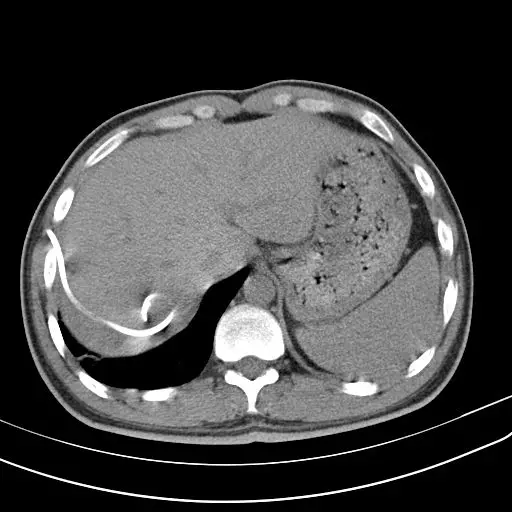

患者急性起病 , 发热、咳嗽、咳痰、痰液粘稠 。

图7-8

你将如何诊断?